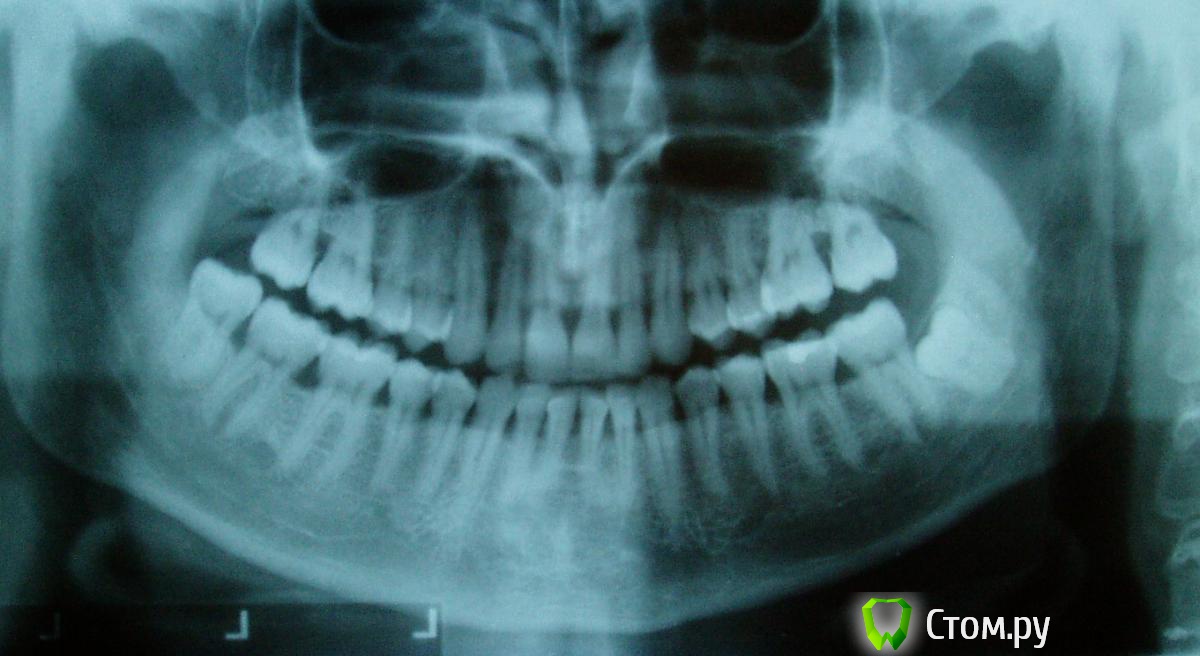

red_butler Опубликовано 15 декабря, 2013 Поделиться Опубликовано 15 декабря, 2013 Я не понял, какое именно правило я нарушил... http://forum.stom.ru/topic/2813-obiazatelno-k-prochteniiu/ Если там ко-то чо-то смог разглядеть, какие бы можно было посоветовать варианты устранения дефекта? Вы сами сомневаетесь в том что по данному снимку можно о чем то судить. Я например клиновидного дефекта не вижу, только рецессию десны ....Дайте нам больше данных : панорамный Rg и более качественные фотоснимки. На вопрос усиления чуствительности я вроде ответил Ссылка на комментарий

Ev127 Опубликовано 15 декабря, 2013 Автор Поделиться Опубликовано 15 декабря, 2013 (изменено) Панорамный снимок полагаю тоже не блещет качеством.Прикус воде как нормальный, по крайней мере этот зуб повышенной нагрузки не испытываетА дефект я так понимаю только в начале пути. Макросъемку высокого качества не позволяет моя мыльница. Протертость есть небольшая. Я ее связываю только с чисткой зубов. Раньше все время чистил в горизонтальной плоскости, особенно клыки(они желтее чем остальные, думал цвет выровняется...) Но раньше он не был таким чувствительным, я его еле-еле и время от времени чувствовал. сейчас невозможно дотронуться в месте дефекта.Я связываю бондинг с повышением чувствительности, потому, что и в процессе и по окончанию чистки зубов у врача я никаких неприятных ощущений не испытывал. Изменено 15 декабря, 2013 пользователем Ev127 Ссылка на комментарий